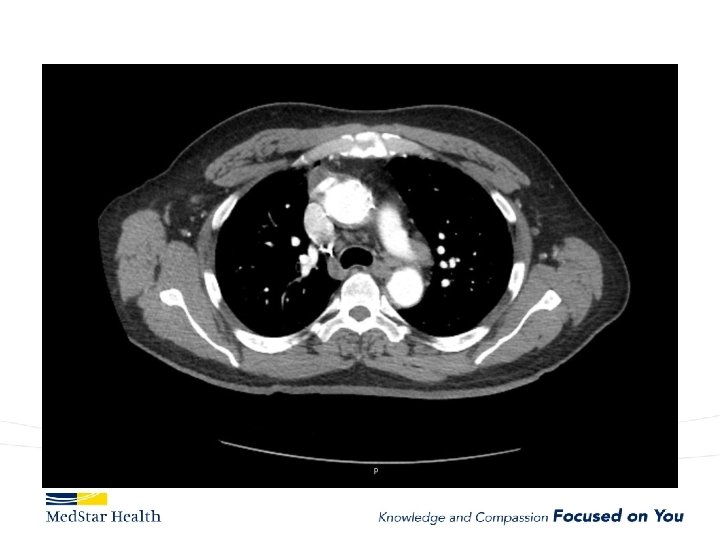

Acute Type B Aortic Dissection • Incidence: 2. 6 -3. 5 per 100, 000 patient-year • Uncomplicated • Complicated – – Malperfusion Rupture Unremitting Pain Uncontrolled HTN

“Uncomplicated” – Type B

Type B Dissection Complicated Uncomplicated Risk TEVAR age, comorbidities Extreme Low Medical Management False Lumen Small, Thrombosed Medical Management Patent/Large(>22 mm), Total Aorta >40 mm TEVAR/adjuncts